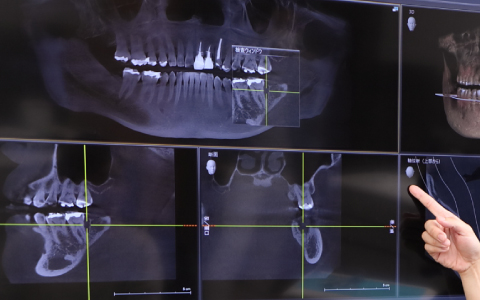

診査・診断・治療計画

診査・診断・治療計画は、オールオン4を成功に導くために必要なとても大事なステップです。

3Dスマイルデザイン、ワックスアップ、ラジオグラフィックガイド等によるプランニングに基づいて、患者様それぞれに合わせたオーダーメイドの治療を慎重に進めていきます。

〜顎の力との調和〜顎の力は非常に強いため、噛むことによって生じる力と上部構造との調和が取れていなければなりません。調和が取れていなければ力に耐えきれずに壊れてしまう場合があります。治療計画・シミュレーションの精度がオールオン4の成功を左右します。

インプラントの埋入位置について、事前に十分なシミュレーションを行っていない場合、その場凌ぎ的に不適切な箇所にアクセスホールを作ることになります。術前の診査・診断・プランニング、咬合力の強さや補綴物のスペースを考慮した治療計画を作成し、ガイデッドサージェリーによってインプラント埋入を行えば、このようなミスは決して発生しません。